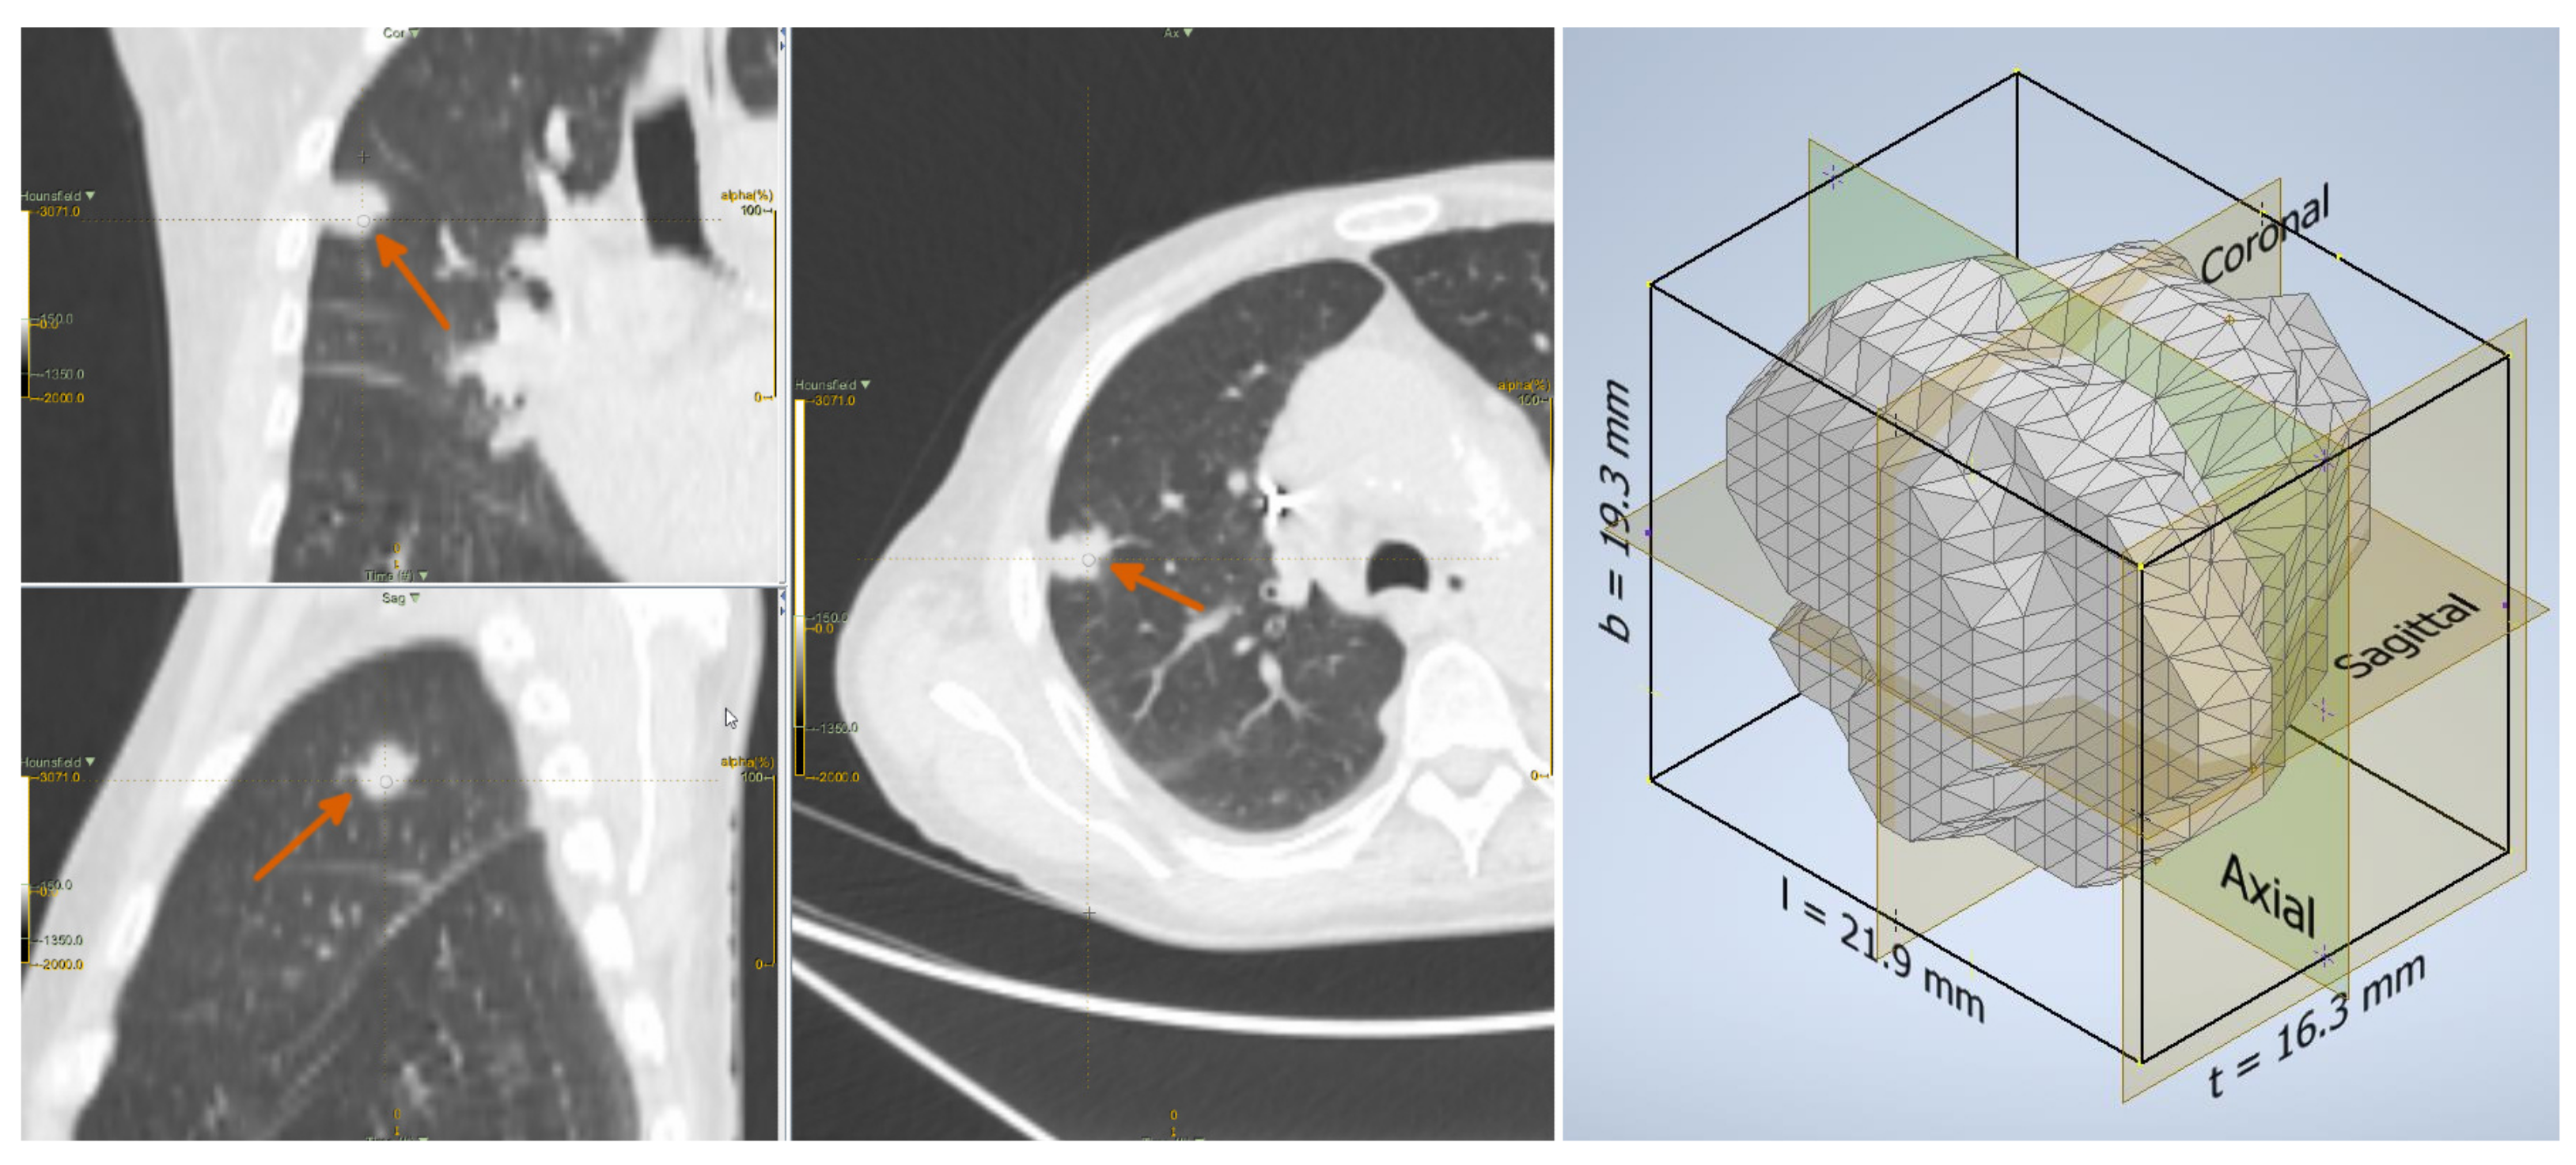

2.2. Lesion Delineation

2.3. Shape Features